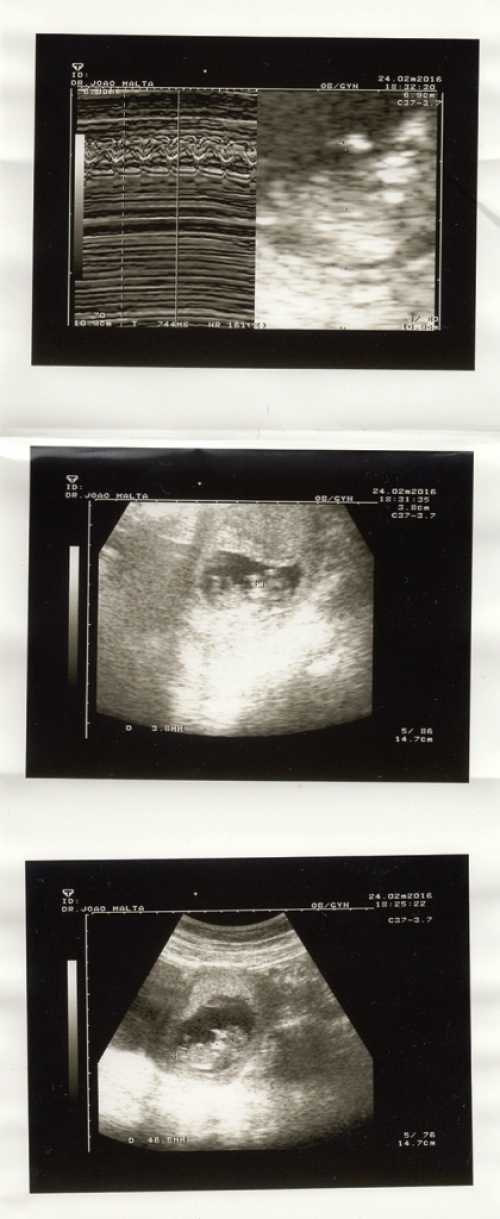

Por ocasião do Dia da Mãe, que se celebra neste Domingo, 1 de maio, publicamos o testemunho de um casal, Sara e João Chambel Leitão, a viver uma gravidez, que ilustra as esperanças e vivências desta etapa na vocação.

Hoje encontramo-nos à espera do nascimento do nosso primeiro filho e recordamos com reverência este triplo sim como o momento central do sacramento que nos alimentou e preparou para o acolhimento desta nova vida. Casámo-nos movidos pelo nosso amor, mas a cada dia desde então confirmamos que nos amamos porque movidos pelo sacramento que recebemos. Não pelos nossos esforços e vontades, mas porque o sacramento recebido nutre em abundância a nossa pobreza e a nossa morte. Nutre-nos de tal forma que o nosso amor até consegue dar frutos – de forma muito concreta, toma agora forma numa nova vida! Maravilha das maravilhas!

Já perdemos a conta da quantidade de vezes que, nestes breves cinco meses de gravidez, nos perguntaram: “E o bebé foi planeado? Ou apanhou-vos de surpresa?” Para nós, é claro. É claro que foi planeado, planeado por Deus, segundo as palavras do salmo “Quando os meus ossos estavam a ser formados, e eu, em segredo, me desenvolvia, tecido nas profundezas da terra, nada disso Te era oculto. Os Teus olhos viram-me em embrião. Tudo isso estava escrito no Teu livro.”

Creio que já não se usa esta expressão tanto como antigamente, mas quando uma mulher está grávida diz-se que está de esperanças. Parece-me uma expressão muito acertada, porque tenho tantas esperanças para este filho! Infelizmente confesso que muitas delas são bastante mundanas (inteligência, beleza, bons horários de sono, etc.), mas procuro sempre centrar-me na única esperança que sabemos que Maria, mãe de todas as mães, pronunciou: “Faça-se em mim segundo a tua Palavra!'. Faça-se em mim e faça-se no nosso filho, sendo que esta segunda parte é tão difícil de dizer! Com o auxílio da Mãe do Céu, procuramos dizê-la, confiando que foi Deus que amou o nosso filho primeiro, e não nós os dois.

Pedimos encarecidamente as vossas orações por esta gravidez. Escutamos com muita frequência o seguinte desejo: “O importante é que venha com saúde.” Certamente que não nos entristecemos com ninguém por desejar para o nosso filho a graça de ser saudável, mas não podemos deixar de ver como se limita a felicidade das nossas crianças a essa condição. Como é que encaramos, realmente, enquanto povo cristão, os bebés que nascem com alguma deficiência ou problema do foro médico? Todos os baptizados são filhos de Deus, chamados a serem santos e felizes! Por isso, pedimos as vossas orações pelos filhos de todas as mães que hoje se encontram de esperanças, para que, neste mundo de 'relações-cortadas' com o Senhor, eles o venham a conhecer e a amar.